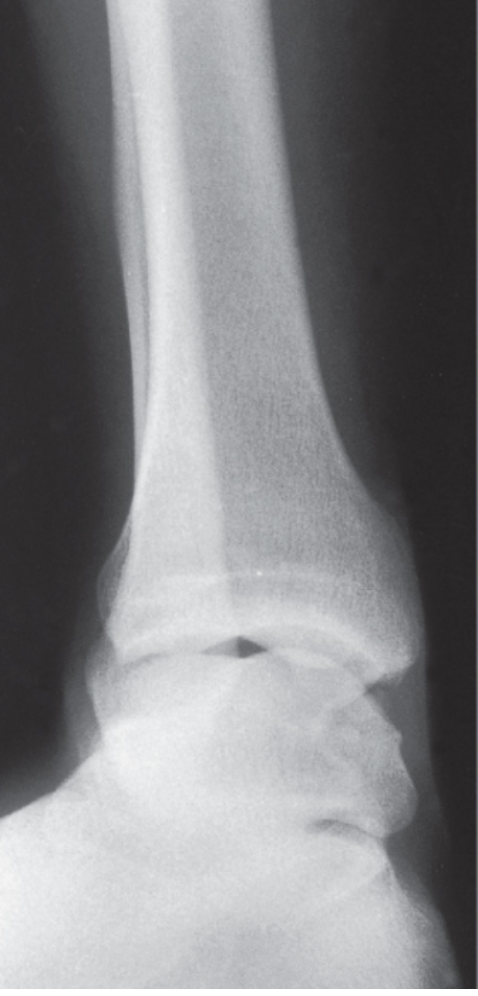

Q

What view is this?

A

Ankle AP